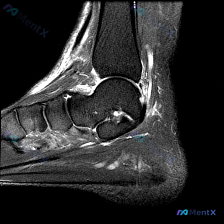

最近遇到这份踝关节MRI读片,看到报告提了软组织积液,整理了完整分析思路分享给大家。 一、病例影像核心信息 这是踝关节MRI T2序列矢状位图像,核心发现整理如下: 1. 骨骼结构:胫骨远端、距骨、跟骨皮质完整,无明确骨折线,无明显弥漫性骨髓水肿高信号 2. 关节结构:胫距关节软骨平整,关节液信号正...

今天分享一例踝关节矢状位T2序列MRI的读片病例,整理了完整分析思路,和大家一起讨论。 病例影像基本信息 检查部位:踝关节MRI-T2序列-矢状位 可见解剖结构:胫骨远端、距骨、跟骨及部分跗骨 核心影像异常表现 1. 骨组织:距下关节跗骨窦区可见高信号影,距下关节面上方伴异常液体信号;跟骨内部靠近跖...